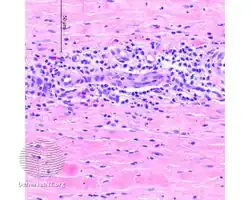

Additional images

Eosinophilic fasciitis/pathology